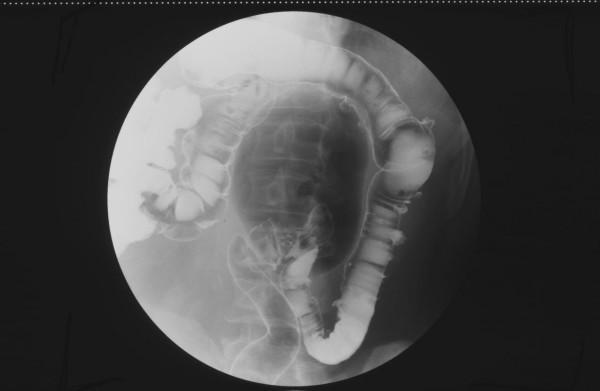

This case series illustrates the clinical presentation and radiological findings of two patients in whom the diagnosis of a Giant Colonic Diverticulum (GCD) was histologically confirmed. We also discuss the pathogenesis and differential diagnosis.

The preoperative diagnosis of GCD is made radiographically, and the importance of the early recognition of radiological findings, especially in asymptomatic disease, is emphasised.

本病例系列阐述了两名经组织学确诊为巨大结肠憩室(GCD)患者的临床表现及影像学检查结果。我们还讨论了其发病机制及鉴别诊断。

GCD的术前诊断依靠影像学检查,强调了早期识别影像学表现的重要性,尤其是在无症状疾病中。